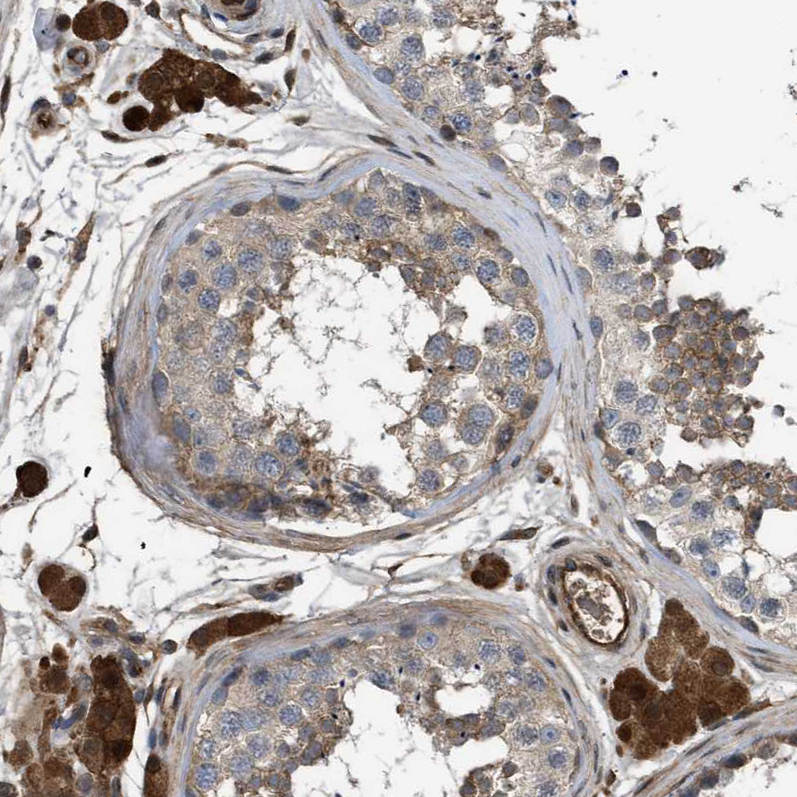

Immunohistochemical staining of human placenta shows strong cytoplasmic positivity in trophoblastic cells.